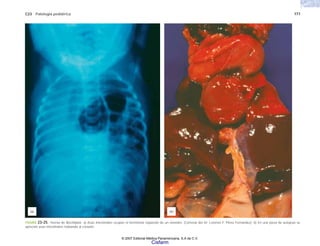

FIGURA 2-3. Aspecto radiológico del esqueleto de un niño recién nacido con

osteogénesis imperfecta grave (tipo I). (Cortesía de la Dra. Sandra Carnevale.)